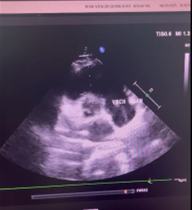

Hình ảnh Giant Eustachian Valve di chuyển trong buồng tâm nhĩ phải trên siêu âm tim của Chị Nguyễn T. V (mũi tên)

👉 Trong quá trình tầm soát, bác sĩ phát hiện chị mắc phải một dị tật bẩm sinh cực hiếm gặp trong buồng tâm nhĩ phải của quả tim, chỉ chiếm khoảng 0,2 % dân số thế giới – Quá phát van Eustachian (Giant Eustachian valve).